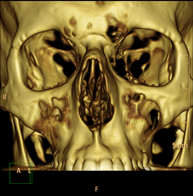

- Facial mass CT

Radiological test that provides high definition anatomical images of the facial mass (face) using CT (Computed Tomography) equipment. Indicated for: tumours, plastic surgery.